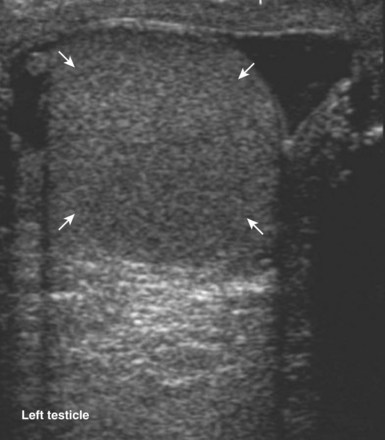

When interacting sound waves are in phase or out of phase, their amplitude will be enhanced or diminished. This pattern of interference is partially responsible for the echo architecture or texture of organs. One pattern of interference, commonly called “speckling” (Fig. 4–19), is seen in organs with fine, internal histology such as the testis.

Figure 4–19 Fine internal echogenicity called “speckle” is caused by scattering of sound waves and the resultant pattern of interference. Note the resulting finely granular, homogenous echogenicity (arrows) of the testicular parenchyma.